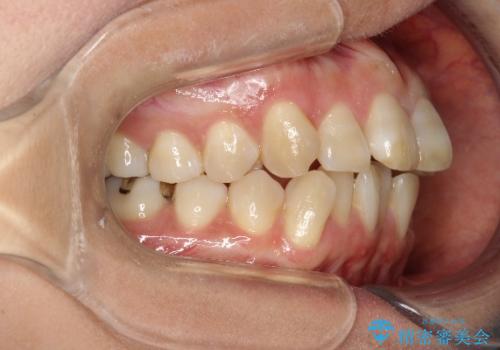

- 初診時には上顎前歯の突出、前歯部の深いかみ合わせ、叢生が見られる状態でした。

インビザラインにて不正咬合の原因除去を行うシミュレーションを念入りに制作の上、治療を行いました。

使用したインビザラインのマウスピース枚数:42枚+25枚+22枚(初回マウスピース+リファインメントが2回、1週間に1枚ペースでの交換)

このケースでは非抜歯にて奥歯を後方に移動させる事で前歯の突出を改善するスペースを作り出していますが、これはマウスピースと顎間ゴムの併用によるもので、患者様のご協力の賜物と言えます。

深い噛み合わせについてはシミュレーション上の結果と、予期される実際の歯の移動量とを考慮し、特殊なセットアップを行う事で望ましい結果を得ることができました。

治療途中でリファインメントという追加のマウスピースを製作する手順を行っていますが、その際に上下の正中を合わせたいとの要望があったため、追加シミュレーションの際に追加でセットアップを施しましたが、無事、上下の正中もご要望通りに改善しています。

使用した装置はマウスピースと顎間ゴムのみです。ワイヤーやマイクロインプラントなど補助装置の使用はありません。